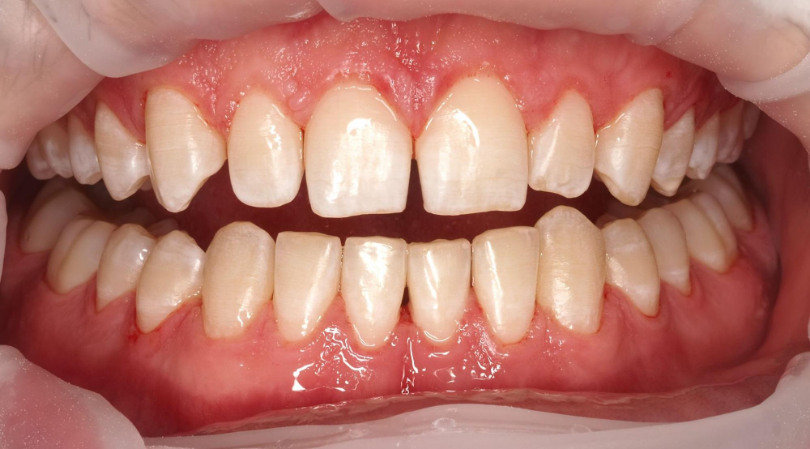

Pacjent zgłaszał się na regularne, co półroczne higienizacje. Wybarwienie płytki nazębnej na pierwszej wizycie ujawniło silne zaleganie płytki nazębnej dojrzałej, kwasowej, gęsto otaczającej zęby (kolor fioletowy). Z każdą kolejną wizytą widać było poprawę higieny i sukces działań higienistki stomatologicznej oraz motywacji własnej Pacjenta. Na trzeciej wizycie po wybarwieniu dostrzegalny jest już tylko delikatny, świeży biofilm. Dzięki technologii GBT posiadamy narzędzia do monitorowania higieny Pacjenta i pozytywnego wzmacniania jego dobrych nawyków.